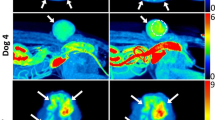

A total of 16 dogs were enrolled. Dog 10 in the [18F]FAZA group had two tumors. Table 1 provides details about the canine patients, including the tumor location, histopathologic diagnosis, and tumor imaging characteristics (SUVmax and TMRmax from the last-time-point images, tumor volume from CT images, and FHV). The mean tumor volumes were 120.06 cm3 for the [18F]FMISO group and 152.26 cm3 for the [18F]FAZA group. Dog 16 was excluded from analysis due to a peribladder artifact that confounded tumor assessment. Tumor hypoxia was detected in 7/8 tumors in the [18F]FMISO group and 4/8 tumors in the [18F]FAZA group. Example images of hypoxic and normoxic tumors (TMRmax < 1.4 on the last image frame) with each radiotracer are shown in Figs. 2 and 3.

CT (left column), PET (middle column), and fused PET/CT (right column) images of canine spontaneous tumors in [18F]FAZA group. Dog 9 (top row): fibrosarcoma (hypoxic) in thoracic wall. Dog 10 (middle row): squamous cell carcinoma (hypoxic) in tongue (white star) and adenocarcinoma (normoxic) in thyroid gland (black star). Dog 12 (bottoom low): soft tissue sarcoma (normoxic) with central necrosis in flank. Stars and arrows indicate tumor locations and hypoxic areas, respectively